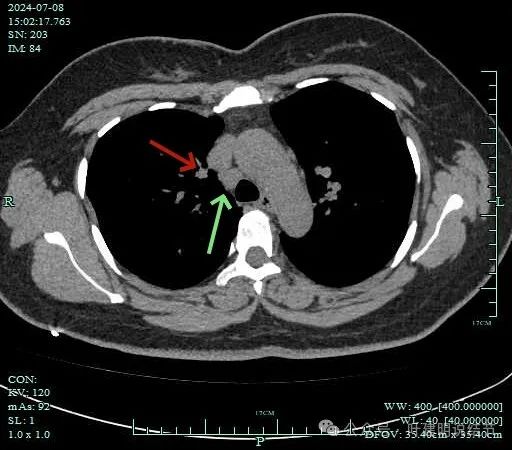

病灶纵隔窗上是软组织影,表面不平,形态不规则。上腔静脉旁有肿大淋巴结。

灶边部分细支气管扩张,腔静脉旁淋巴结较大

病灶有血管与之相连,淋巴结更显得明显了。